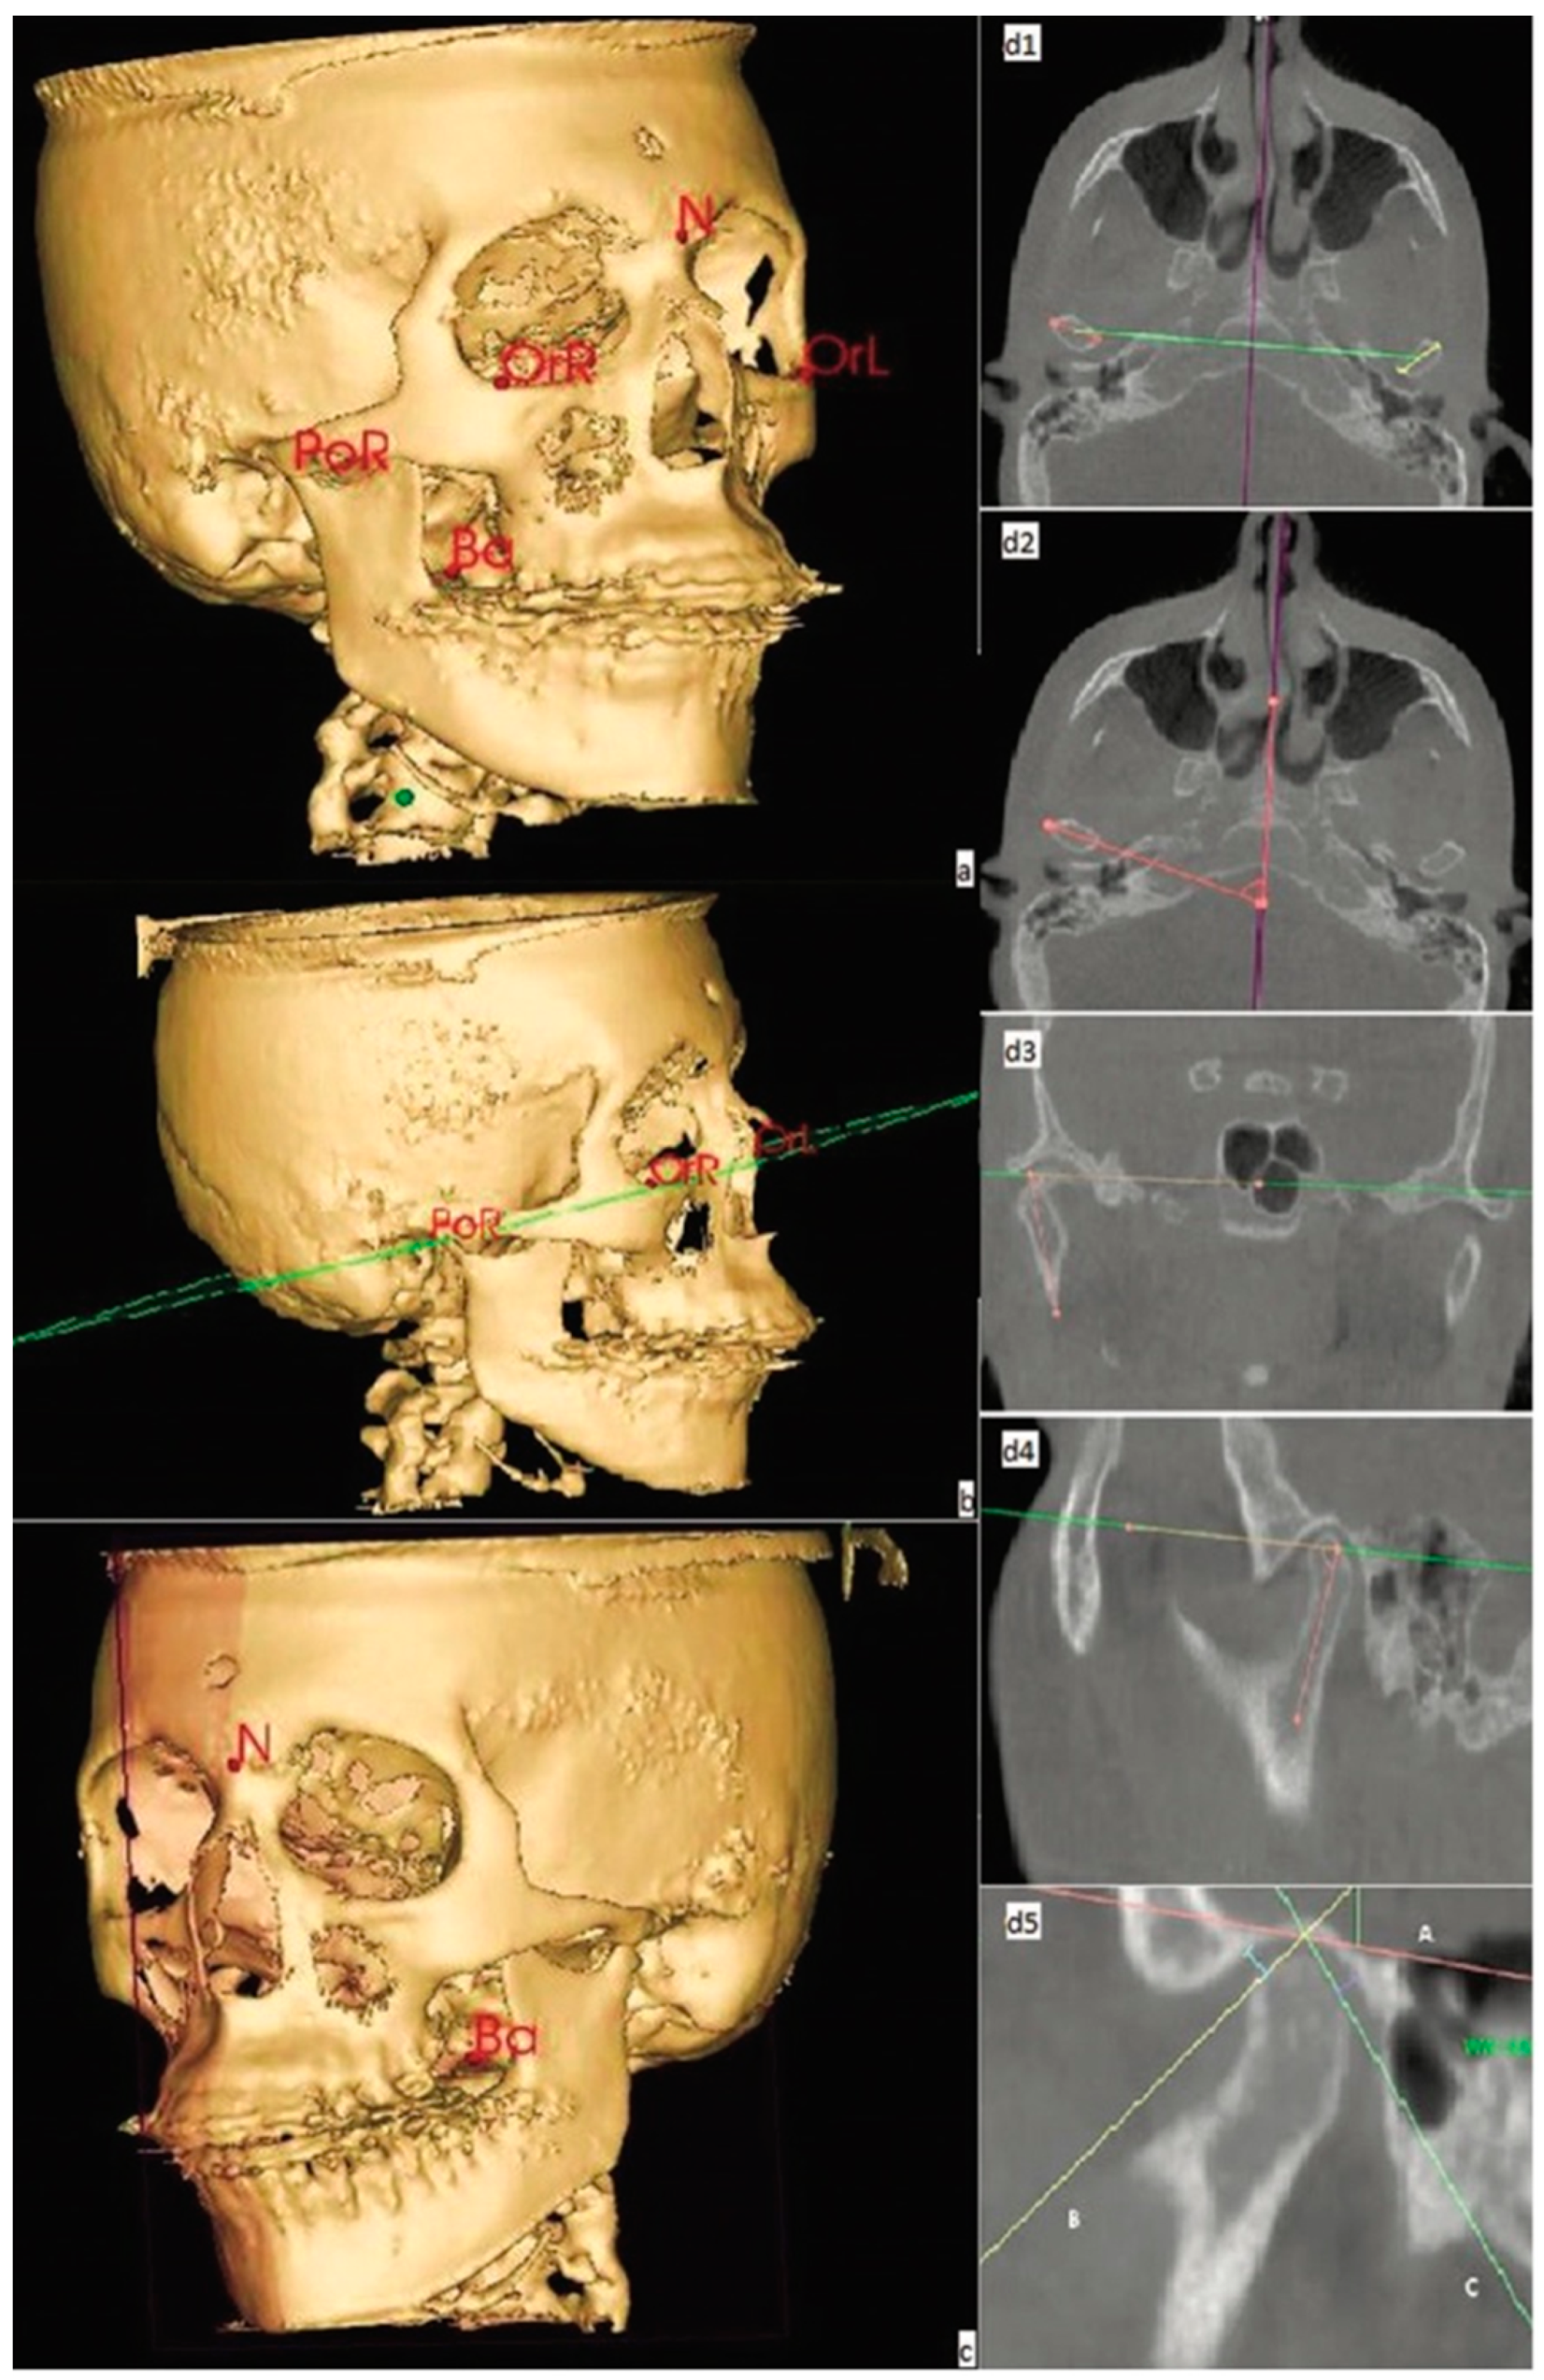

2. Materials and Methods